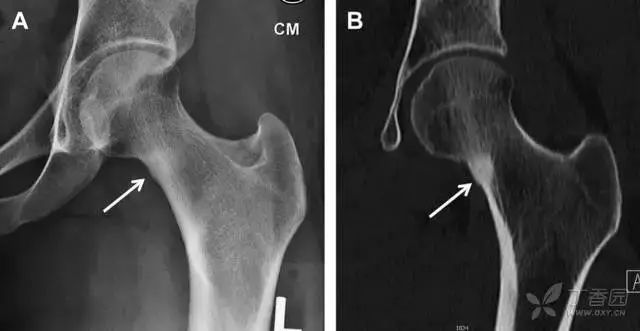

05股骨近端骨折

股骨颈骨折常发生在老年人,头下型骨折最常见,但是当股骨外旋或有明显的关节炎骨赘形成时,骨折较难发现。此外,肥胖和骨量减少增加髋部 X 片诊断难度,所以需格外注意。

因骨结构重叠影响,股骨转子骨折发生轻度移位时亦很难发现,加做一个不同角度的 X 线片有助于诊断(图 7)。

图 7 摔倒后股骨大转子骨折。A 正位片初步检查未发现明显骨折,进一步检查发现大转子上方皮质中断(箭头)。B 蛙式侧位片示骨折分离,尤其是后方(箭头)。初步检查时忽视了这一点,是因为股骨颈未能充分显